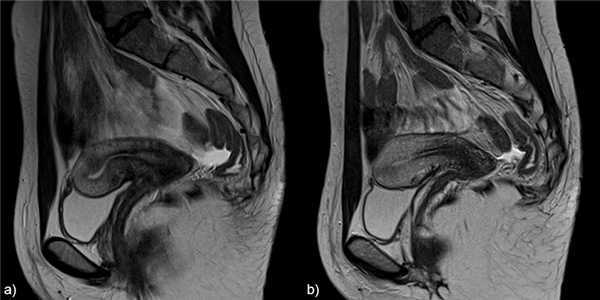

До сих пор неясно, наблюдается ли повышенная заболеваемость аденомиозом у женщин, получавших тамоксифен, или существует спектр тамоксифен-ассоциированных кист, имитирующих особенности аденомиоза (аденомиозоподобные изменения).![]()

Рис.13 Аденомиома: а) сагиттальный Т2 и b) аксиальный Т2-взвешенные изображения, неоднородная гипоинтенсивная на T2 масса с плохо определенными границами, мелкими гиперинтенсивными фокусами в структуре (белые стрелки).

![]()

Рис.14 Лейомиома: а) сагиттальный Т2 и b) аксиальный Т2-взвешенные изображения, неоднородная гипоинтенсивная на T2 масса с четко определенными границами, масс-эффектом на окружающие ткани (звездочка). Есть также особенности, наводящие на мысль о аденомиозе.

Рис.15 Наружный аденомиоз: корональные T2 взвешенные изображения, субсерозная плохо отграниченная масса с низкой интенсивностью сигнала, мелкими гиперинтенсивными фокусами в структуре в левой стенке матки (белая стрелка), имитирующая эндометриоз. Также видны лейомиомы (звездочки).

Рис.16 Тамоксифен-ассоциированные аденомиозоподобные изменения: сагиттальные T2 взвешенные изображения, множественные кисты выстланные атрофированным эндометрием, локализованные на границе эндометрия с миометрием.